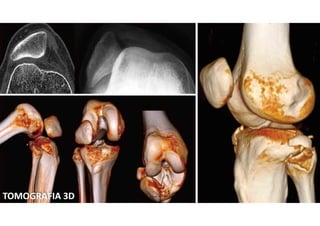

O QUE É?

 Tomografia computadorizada é um procedimento não

invasivo de diagnóstico por imagem que combina o uso de

raio-x com computadores especialmente adaptados. É

utilizado para criar imagens detalhadas dos mais variados

tecidos do corpo humano.

 O procedimento é realizado através da emissão de raios X

rotacionada ao redor do corpo, que por sua vez e de forma

variada, a depender de cada tecido, atenua o feixe de raios-

X, que são absorvidos por detectores de radiação, que

enviam então os dados para um sistema computacional.

PECULIARIDADES

 A tomografia não oferece riscos ao paciente quando obedecida a periodicidade

e as recomendações do profissional responsável pelo exame.

 Por se tratar de um procedimento que utiliza raios-x para criar as imagens, é

fundamental não ultrapassar a dose anual de radiação recebida por esse tipo

de exame. Por isso, sua quantidade deve ser registrada no laudo. O recomendado

é que seja realizada no máximo uma vez por ano.

 Os maiores riscos que o paciente está sujeito ao realizar a tomografia estão

relacionados ao não cumprimento das orientações do médico ou técnico, que

pode desencadear uma reação ao contraste, por exemplo.